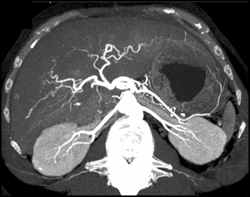

Diagnosis

Hepatoma